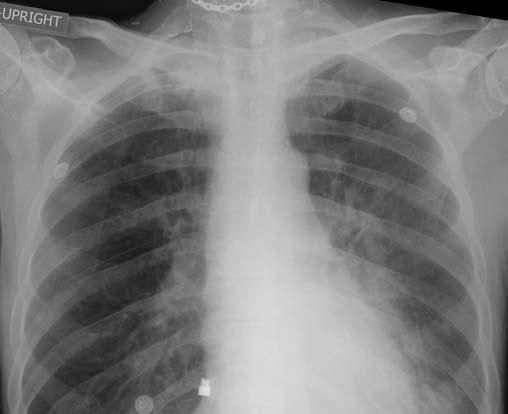

A chest radiograph suggested only scarring in the apex of the right lung (Figure 1); however, a CT scan revealed a thin-walled cavity, measuring approximately 3.9 cm in diameter, with several small adjacent satellite nodules (Figure 2). Acid-fast smears of 3 expectorated sputum samples showed no organisms, and Gram staining showed normal upper respiratory tract flora with a few WBCs.